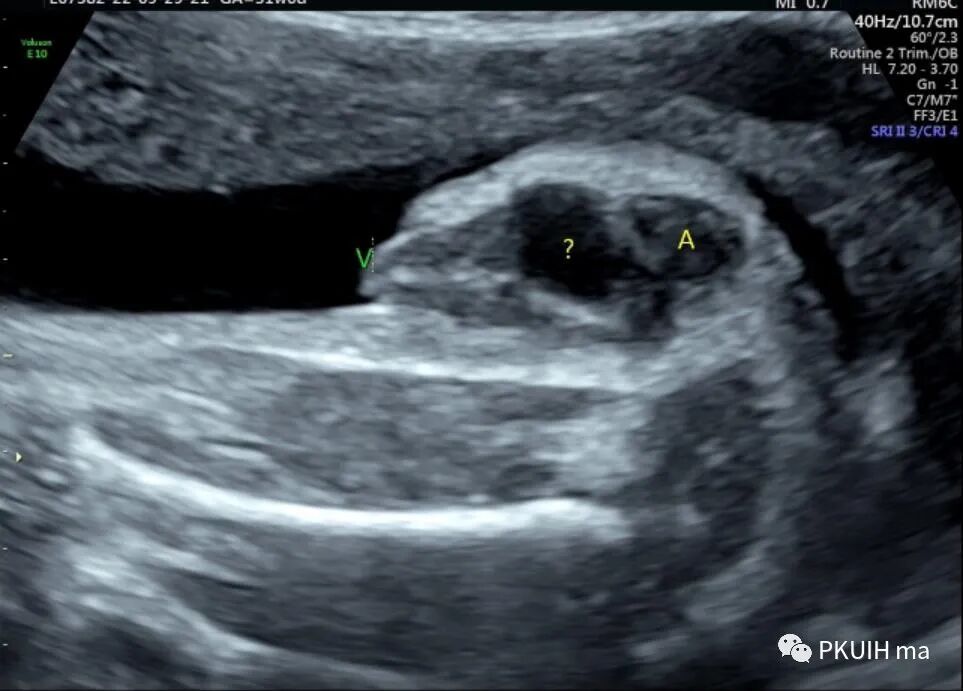

胎儿臀位,改用经阴道超声检查,囊性包块边界清晰,与周围组织分界清。

结合以上图像考虑为处女膜闭锁合并阴道积液,由于包块不规则不能除外合并阴道斜隔等其他异常。